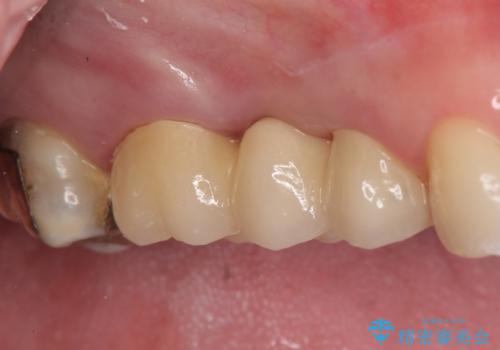

診査の結果、歯根が破折しており保存不可能だったため抜歯し、ブリッジによる補綴を行いました。

今回用いたオールセラミッククラウンはジルコニアフレームという白い素材の上にセラミックを盛っているため、審美性が非常に高いのが特徴です。

また、ジルコニアは人工ダイヤモンドの材料にも使われているほど高い強度を持っており、そのためオールセラミッククラウンは審美性だけでなく、奥歯やブリッジの補綴も可能とするクラウンです。